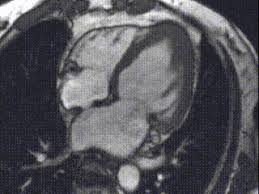

Combined Electrocardiography Coronary Angiography And Magnetic Resonance Imaging For The Diagnosis Of Viral Myocarditis A Case Report

Combined Electrocardiography Coronary Angiography And Magnetic Resonance Imaging For The Diagnosis Of Viral Myocarditis A Case Report from www.spandidos-publications.com

Journal of the american college of cardiology vol. More specifically, it is described as. Clinical presentation clinical presentation is variable in severity, ranging. Myocarditis cardiosclerosis is a pathology in which parts of the myocardium involved in inflammation die and are replaced by connective tissue. Mrt in der diagnose und monitoring neurodegenerativer erkrankungen. Khk, ischämietest bei bekannter khk). It is considered the most. Sie kann akut oder chronisch verlaufen.